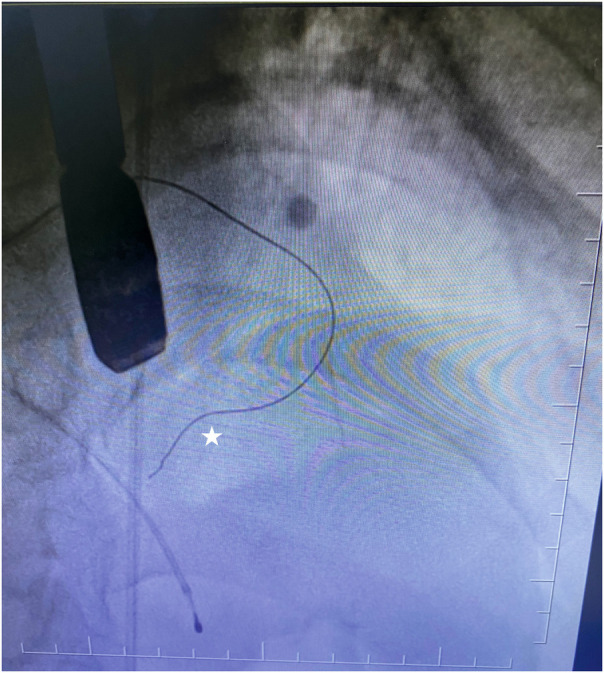

Methods: This study included 14 patients (8 females, 6 males), with symptomatic hypertrophic obstructive cardiomyopathy who underwent ASA between the years 2017 and 2025. Because of the unavailability and the high cost of contrast agents in our country, we used practical physiological agents, which comprised a cocktail fluid (agitated 5 mL of saline plus 0.5 mL blood of the patient). We injected ethanol (absolute alcohol 96%-99%) into the target perforatory artery using transesophageal echocardiography (TEE) in a step-by-step manner to observe a reduction in mitral regurgitation and QT prolongation at electrocardiographic monitorization (initially, 0.5 mL alcohol, then by increasing the dosage up to 3 mL).

Results: We clearly obtained a good myocardial opacification of the interventricular basal septum border with our cocktail contrast agent. Furthermore, we used TEE in the ASA procedure, unlike other researchers who reported on this procedure. No arrhythmias and allergic reactions were recorded during the administration of the contrast agent. The mean dose of alcohol administered during ASA was 2.1 ± 0.7 mL. The procedural rate of success was highest (100%). We assessed the effectiveness of the treatment in terms of a reduction of the peak left ventricular outflow tract gradient and the disappearance of severe mitral regurgitation with a significantly systolic anterior motion.